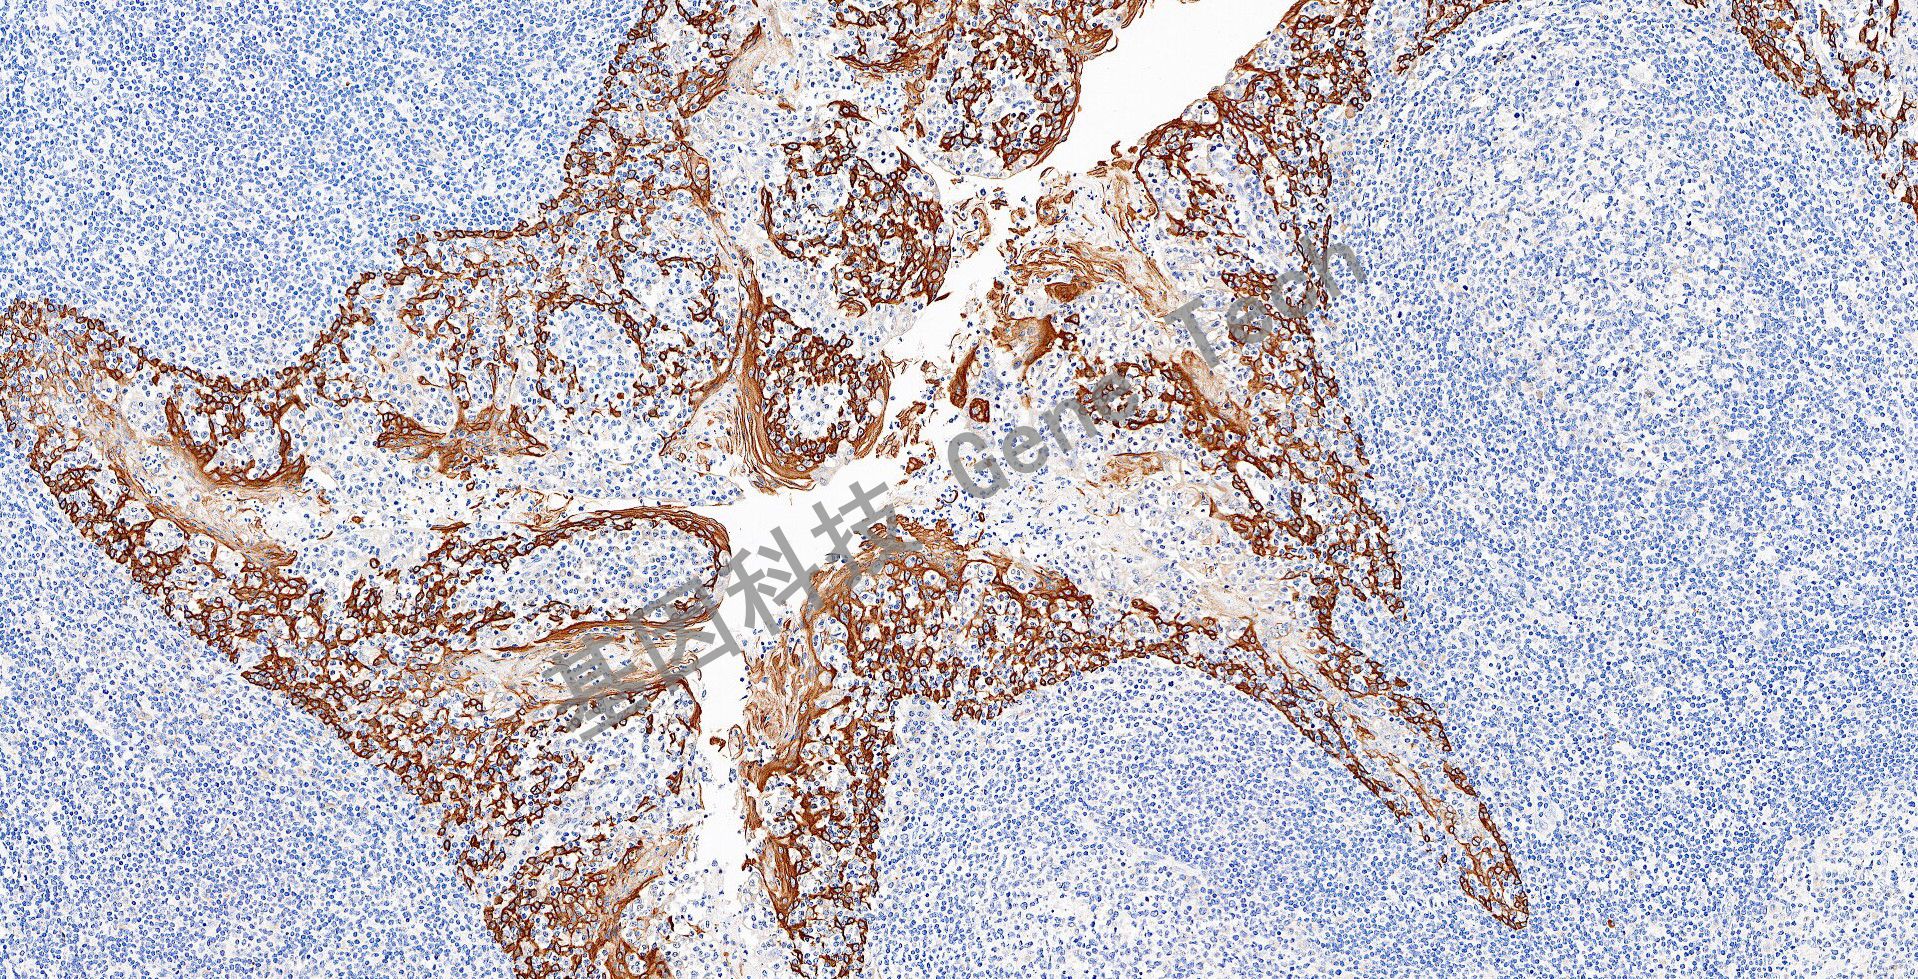

食管石蜡切片,用 CK16(GT2228)染色,细胞浆阳性,DAB 显色。